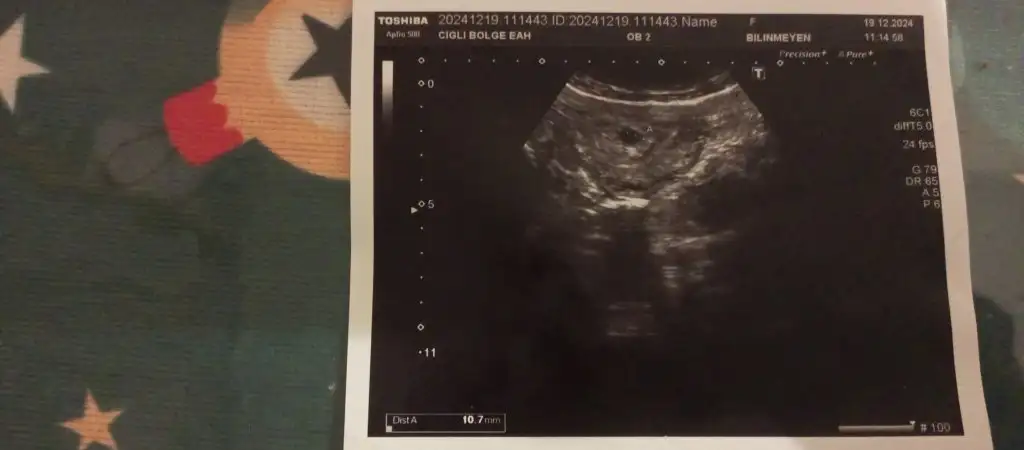

Her hamilelikte farklı oluyor aynı kişi olsa bile, hiç beklemiyorduk yine oldu,o kadar uğraştığımızda olmamıştı.Doktorlara göre 35 yaş mıydı neydi son yaş gebe olmak için veya çocuğunuzun olması mümkün değil diyorlar bir bakmışız hamileyim, Allah ol derse olur,her şey olacağına varır.Sol altta Dist A 10.7 mm çıktı bir de benim, resmini de atayım

Sonuç 9 .haftadaydım boş gebelikten kürtaj oldum yani hormonlarım dediğim gibi durmuştu göğüslerim ilkinde olduğu gibi tam şişmedi şüphelenmiştim, rüyamda da düşük yaptığımı görmüştüm, birkaç gün sonra sarı lekeli kan akıntısı gelmeye başlamıştı 2 gün üst üste olunca doktora gittim, acilde ultrasona da baktılar bozulmuş kese dedi doktor bey,4 ay sonra yine hamile kaldım çok şükür bu defa normalmiş bugün ultrason görüntüsünü de aldım 6+1

Unutkanlık oldu bende de iyice, parça parça yazıyorum.Bu arada 2.gebeliğim boş olduğu için hormonlarım bir anda durdu göğüslerim ilk gebelikteki gibi tam şişmedi bunu doktora da bu şekilde demiştim,6.haftada şişmeye başlıyorlar yanlardan :) benim şuan 6+2 umarım sonu da hayırlı şekilde olur,olursa bir hayır olmazsa bin hayır derler,2.gebeliğimi istemedim maddi manevi her yönden olmadı da zaten...ama bu defa istiyorum kendimi gerçekten kadın gibi görmek istiyorum,bakabileceğime de emin oldum ,genetik göğüs küçüklüğü var maalesef benim ancak hamilelikte şişiyor 😹